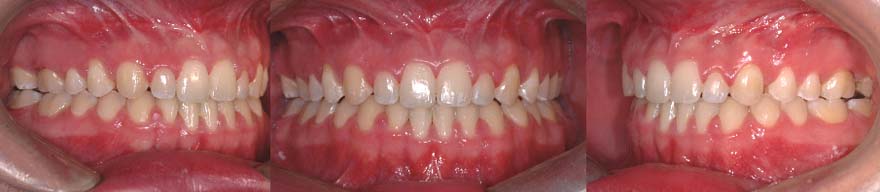

(A) Béance antérieure causée par un excès postérieur vertical du maxillaire. Seules les dents postérieures se touchent lors de la fermeture de la bouche. (B) Coupe pour une impaction maxillaire différentielle. La partie rouge sera enlevée (ostectomie). (C) Le segment maxillaire est remonté et fixé à l’aide de plaques et de vis. Il en résulte une auto-rotation mandibulaire qui fait remonter et avancer la dentition inférieure. (D) Une fois le traitement terminé, la béance est fermée et les dents se touchent partout.